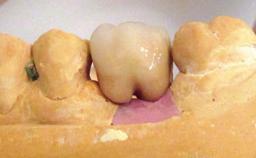

Excess Cement Resulting in Peri-implant Infection Presenting as a Draining Sinus Tract

Biological complications caused by undetected cement residue have been receiving much attention. Excess cement might be responsible not only for rapidly developing of peri-implantitis, but also for delayed or chronic manifestations of the disease many years after cementation (Wilson 2009; Linkevicius and coworkers 2013). Invitro and clinical studies have shown that it is very difficult or even impossible to completely clean up excess cement at subgingival margins, so popular in cemented restorations (Agar and coworkers 1997; Linkevicius and coworkers 2011, 2012). Possible outcomes of biological complications due to excess cement range from temporary inflammation of the peri-implant soft tissues without any serious esthetic and functional consequences all the way to implant loss. This report describes a case of peri-implantitis caused by residual cement; as well as the management and quite unusual resolution of the complication. The patient presented in 2009 with a draining sinus tract, tenderness on chewing, and tissue contact above the implant-supported restoration. The implant had been restored approximately three years before.